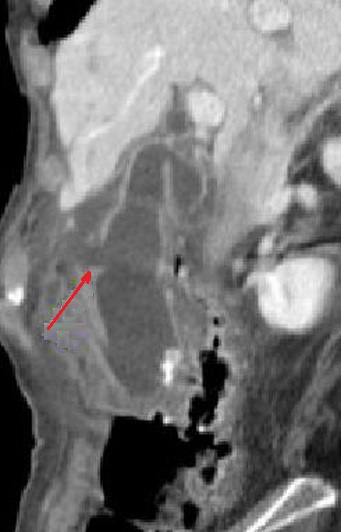

Signe direct de

cholecystite gangreneuse perforee ( fleche rouge ) .

La rupture de paroi vesicule \est en vue tres nette

sur image TDM coupe coronal . La presence de

l'air para vesiculaire se verifie la perforation

|